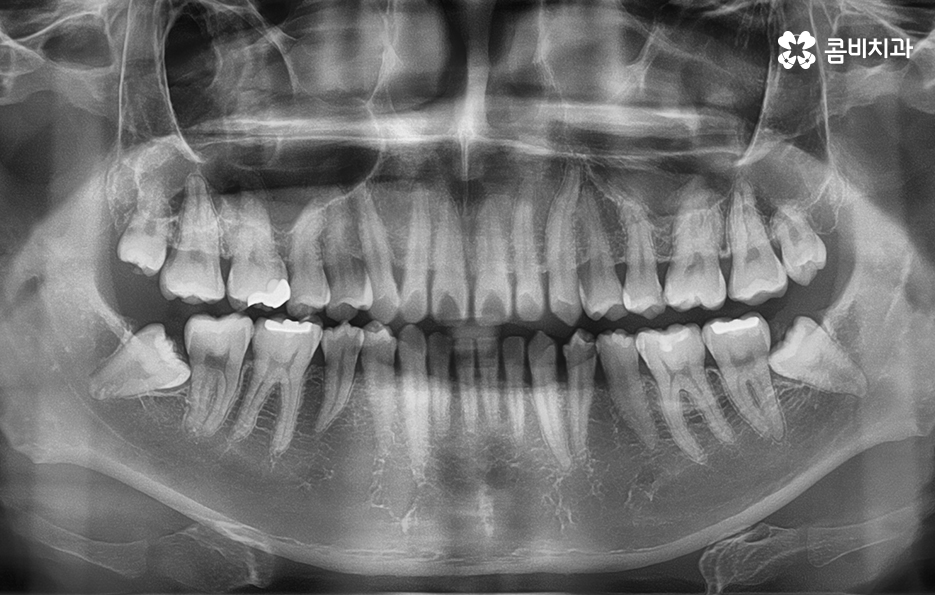

교정 장치를 선택하기 전에 골격 상태와 치열, 얼굴형 등을 먼저 정밀 검진해야 합니다.

위 사례의 경우 앞니만 치아부분교정 통해서 치료가

이뤄진 사례로 치아의 돌출 여부나 골격, 교합 등을

고려하여 큰 문제 없이 치료가 가능했던 사례입니다.

위 사례의 경우 유독 앞니 위주로 치아가 벌어져 있는 상태이며

옆모습의 경우에도 비교적 양호한 상태입니다.